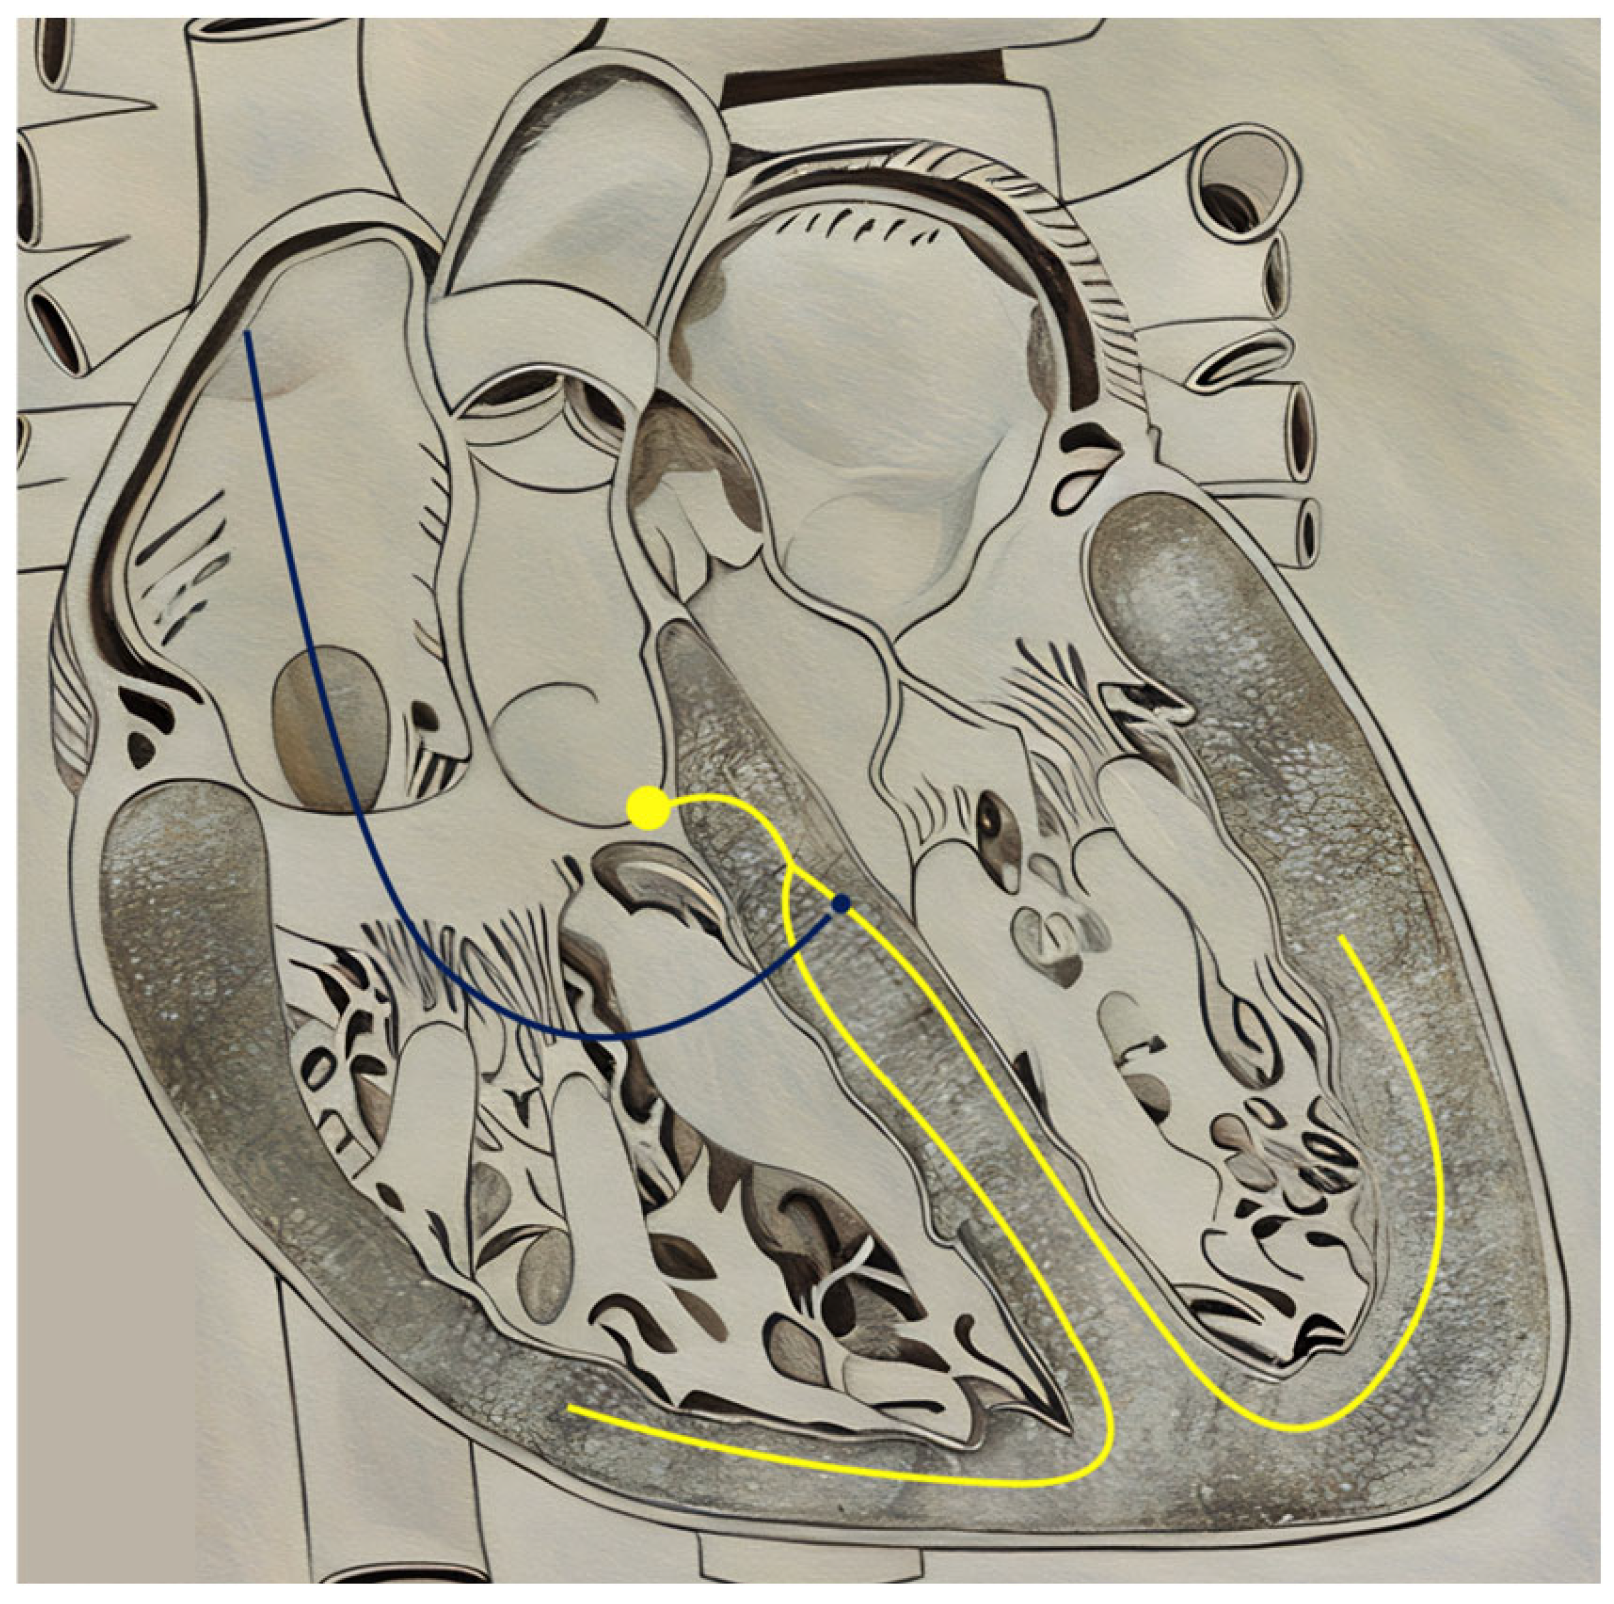

5.2. Left Bundle Branch Area Pacing

6. A Route Revisited: Endovascular Lead Placement